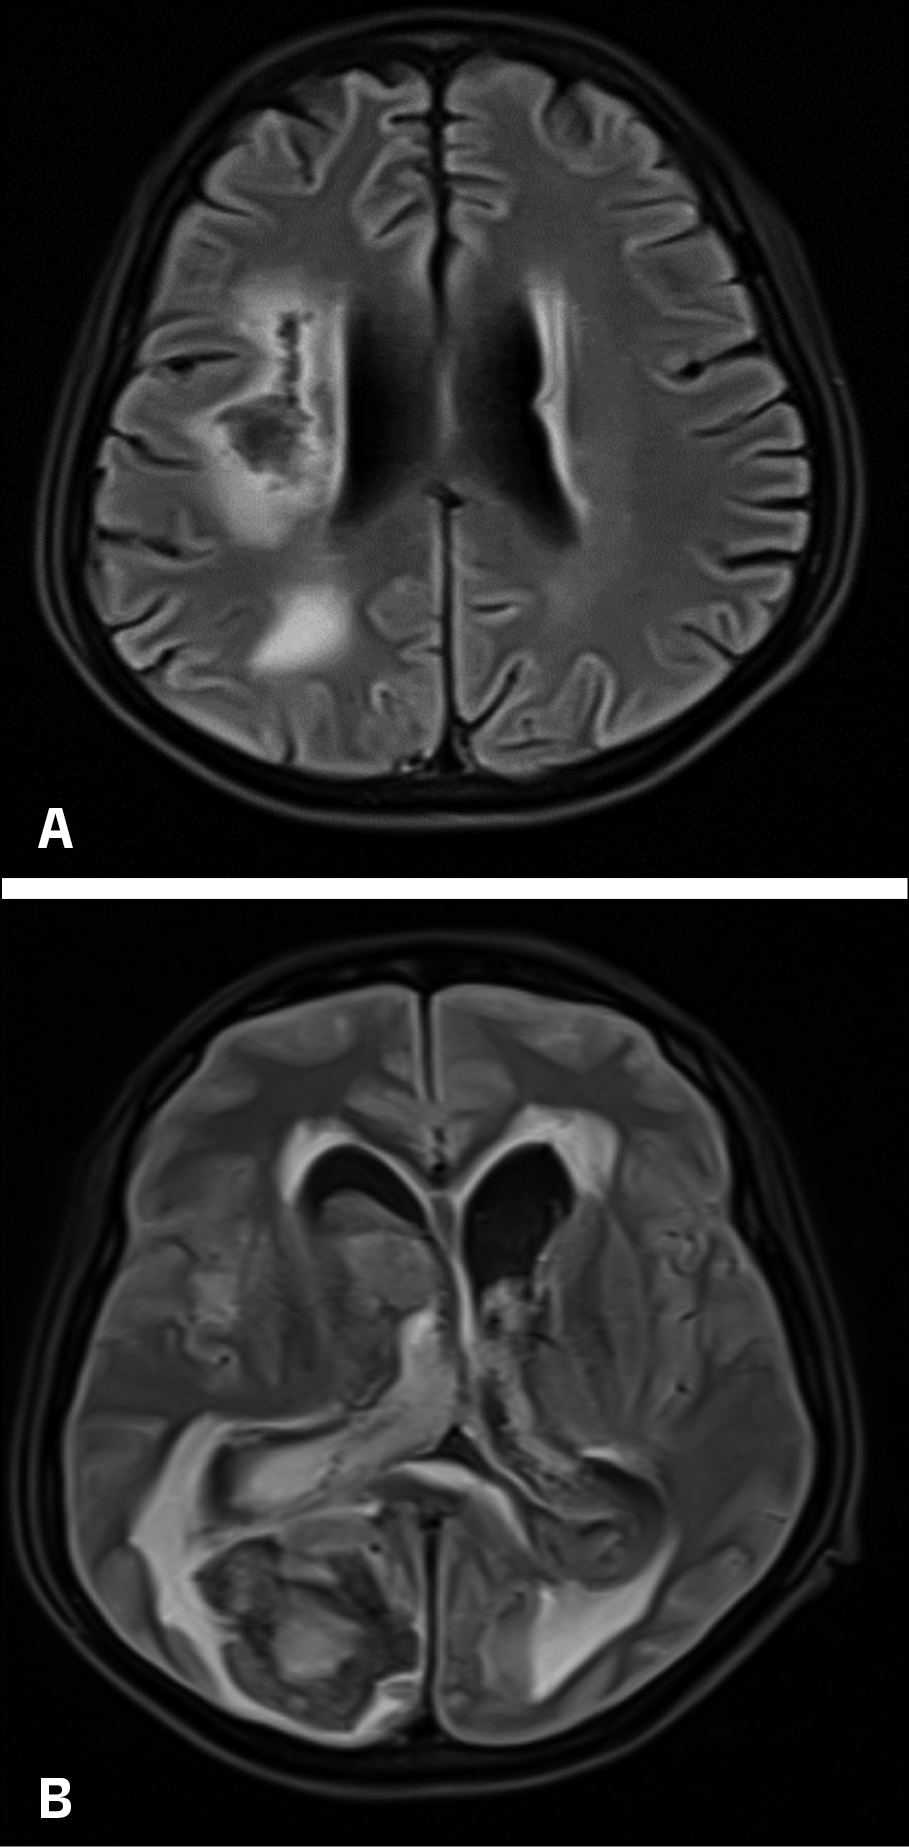

However, on day 16, the patient experienced a sudden neurological decline, characterized by severe headache, projectile vomiting, bradycardia (54 beats/min), and hypertension (190/110 mmHg). Glasgow Coma Scale (GCS) assessment revealed a score of less than 8, necessitating immediate intubation. MRI showed acute massive bi-ventricular haemorrhage (IVH) with midline shift to the left and hydrocephalus (Figure 3A and 3B).

Figure 3A and 3B - MRI showed acute massive bi-ventricular haemorrhage (IVH) with midline shift to the left and hydrocephalus.